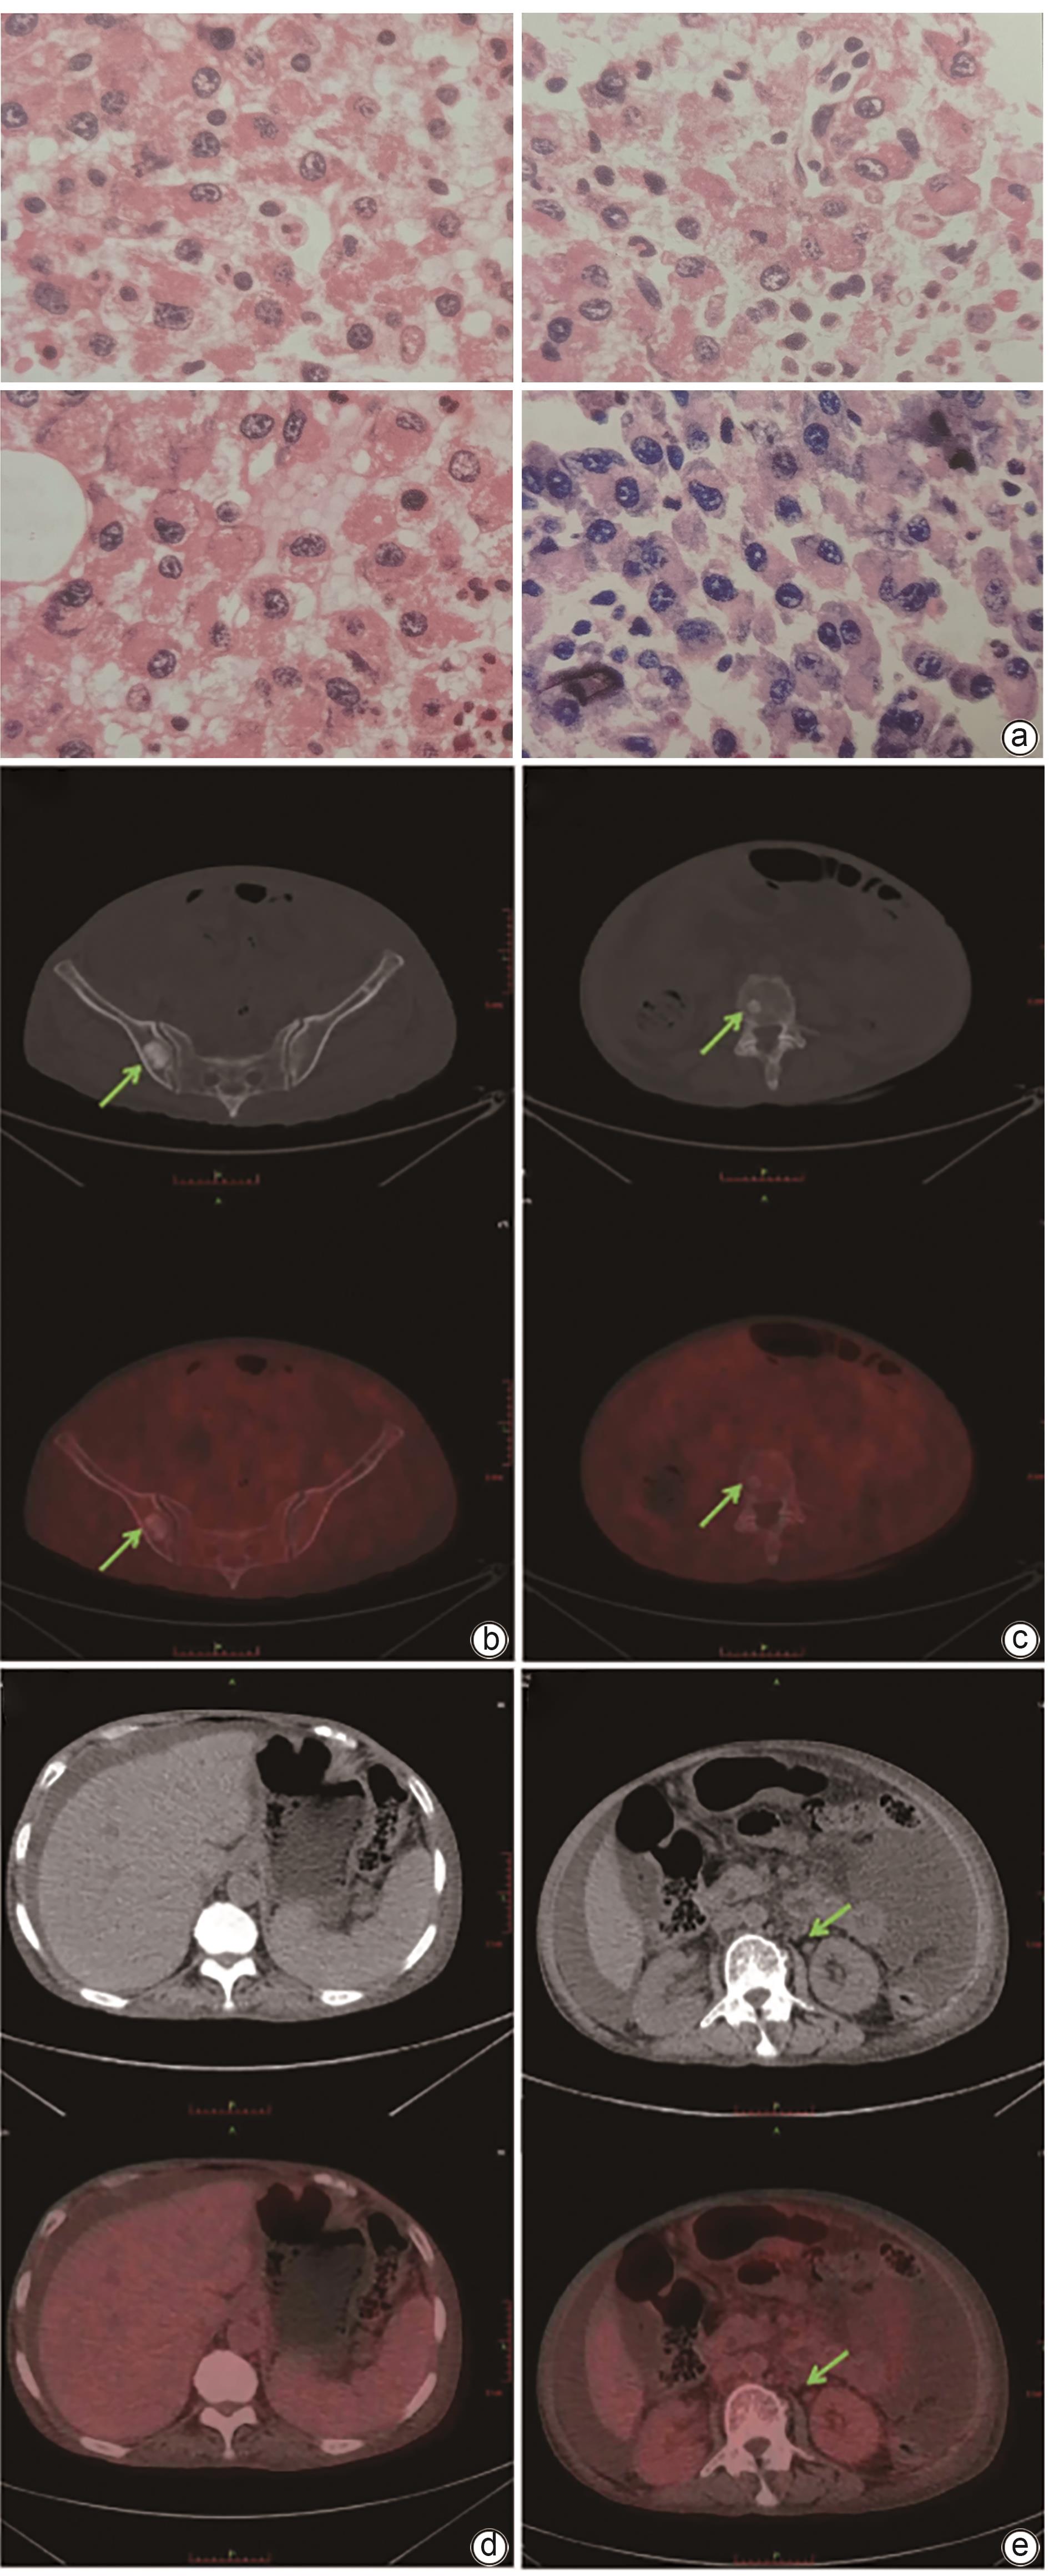

• POEMS syndrome is a rare condition associated with plasma cell disorders, and it often involves multiple systems and has diverse clinical manifestations. This article reports two cases of POEMS syndrome with hepatosplenomegaly as the initial manifestation. During the course of the disease, the patients presented with lower limb weakness, hepatosplenomegaly, lymph node enlargement, ascites, hypothyroidism, positive M protein, and skin hyperpigmentation, and 18F-FDG PET-CT imaging revealed bone lesions mainly characterized by osteolytic changes and plasma cell tumors. There was an increase in the serum level of vascular endothelial growth factor. The patients were finally diagnosed with POEMS syndrome, and the symptoms were relieved after immunomodulatory treatment.